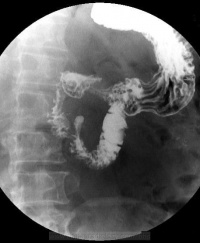

1.X线钡餐检查:可发现十二指肠憩室表现为突出于肠壁的袋状龛影,轮廓整齐清晰,边缘光滑。加压后可见龛影中有黏膜纹理延续到十二指肠,有的龛影在钡剂排空后,见到为憩室腔内残留的钡剂阴影较大的憩室,颈部较宽,在憩室内有时可见气液面。当憩室周围肠黏膜皱襞增粗,轮廓不整齐,局部有激惹征象或憩室排空延长,或有限局性压痛,认为是憩室炎的表现,如憩室固定不能移动,是有憩室周围炎的表现。

继发性十二指肠憩室常伴有十二指肠球部不规则变形并有肠管增宽阴影。当憩室较小或颈部狭窄,其开口部常被肠黏膜皱襞掩盖,或憩室内充满大量食物残渣,而不易发现憩室的存在,

如有少量钡剂进入憩室或可见一完整或不完整的环影。用低张十二指肠X线钡剂造影可增加憩室的发现率。